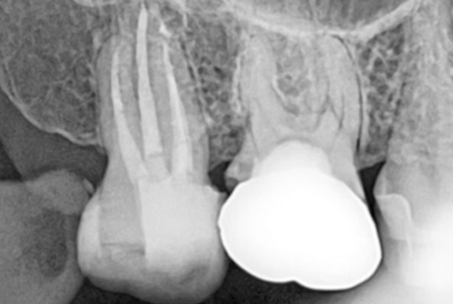

위 사진들은 현직 치과의사들이

저희 웃는얼굴 치과에서 치료 받은 실제 사례들입니다.

비 전문가 눈에는 그냥 흔한 엑스레이 사진일 뿐이겠지만

치과의사들이라면 알아챕니다.

저 치료가 얼마나 난이도 있는 치료였는지,

얼마나 정성이 들어갔는지를 말이지요.